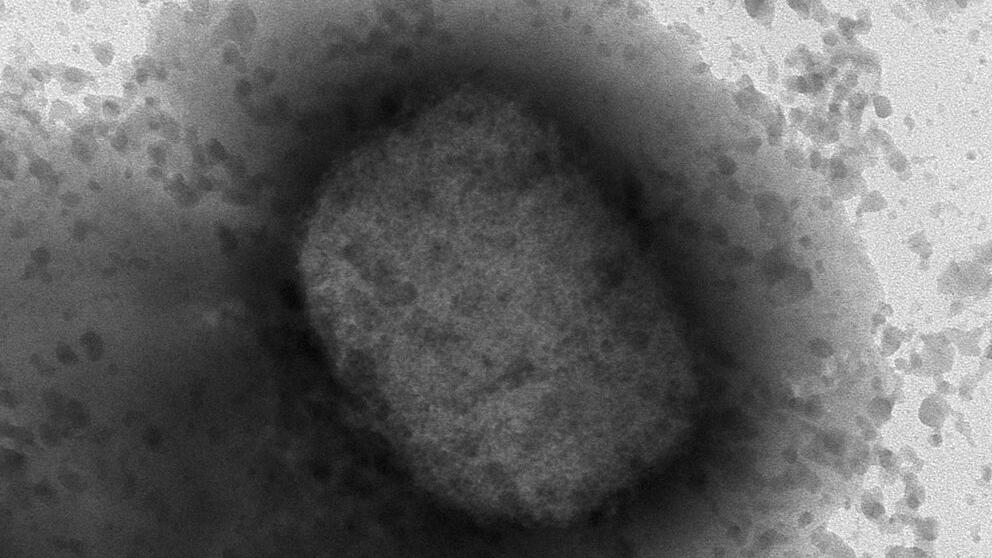

中、西非流行的猴痘症傳入歐美,患者身上會出疹和發燒。(美聯社)